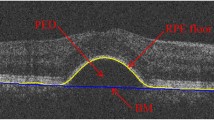

This paper presents a novel method for automated detection of retinal detachment from ocular ultrasound image using digital image processing and computational techniques. Retinal detachment (RD) is an ocular emergency in which retina gets detached from the tissues lying underneath it and often requires immediate intervention to prevent rapid, irreversible vision loss. Direct fundoscopy and visual field testing are most common methods for the detection of RD. These methods are difficult to perform and they do not completely rule out retinal detachment. Generally, Ophthalmologists use ocular ultrasound to enhance their clinical acumen in detecting RD. Sometimes it is difficult to extract diagnostic features from ultrasound (USG) images due to its poor quality. Also, noise present in the image would cause misinterpretation during visual inspection;this demands development of intelligent and automated techniques for detection of retinal detachment. Further, the paper proposes a novel frame work for accurate and automatic retinal detachment using image processing techniques and mathematical analysis of detached area contour detected within the ocular globe. Furthermore, the estimation of diagnostic parameters, indicative of retinal detachment is also computed. Based on the mathematical analysis, three such parameters, percentage area of detached retina (PADR) compared to the ocular globe, angular width of detachment (α) and maximum radial distance of detachment to choroid layer beneath it (β), are calculated. These estimated parameters are very useful in determining the exact location and extent of retinal detachment. Results obtained through the proposed retinal detachment detection scheme are validated by the radiologist.